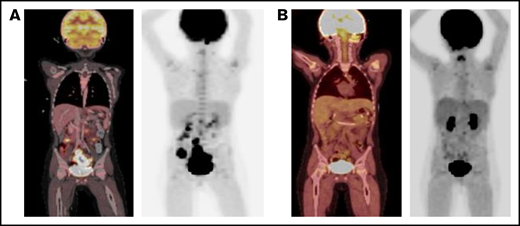

PET scan response before and after blinatumomab treatment. (A) PET scan on day +92 showing concern for PTLD with multifocal, fluorodeoxyglucose-avid uptake and lymphadenopathy in the abdomen and pelvis. (B) PET scan on day +179 showing significant metabolic and structural improvement of abdominal and pelvic lesions 1 day after completion of blinatumomab. PET, positron emission technology; PTLD, posttransplant lymphoproliferative disease.

Routine plasma EBV polymerase chain reaction surveillance first showed a viral presence (1783 IU/mL) on day +63. The patient was admitted on day +85 with fever, abdominal pain, and marked EBV viremia (29 585 IU/mL). Weekly rituximab therapy was initiated, the serum tacrolimus prophylaxis goal was decreased to 5-8 ng/mL, and abatacept was discontinued. A positron emission tomography (PET) scan showed multifocal lymphadenopathy in the abdomen and pelvis, concerning for PTLD (Figure 1A). A core biopsy of the abdominal mass on day +100 confirmed monomorphic PTLD, diffuse large B-cell lymphoma subtype, EBV positive, with immunohistochemical stains expressing PAX5, CD30, CD45, CD79a, BCL6, MUM1, and EBER, but not CD3, CD10, CD138, TDT, HHV8, or ALK1. CD20 was positive in a small subset of cells. After 3 doses of rituximab, a second PET scan demonstrated increasing size of the abdominopelvic lymph nodes and new liver lesions.

Given this disease progression and the desire to avoid cytotoxic chemotherapy in a patient with FA, we administered EBV active, HLA-A24–restricted match (Michael D. Keller, Jeffrey Modell Diagnostic and Research Center for Primary Immunodeficiency Disorders at Children's National Health System, e-mail, 3 January 2021 and 2 January 2022 ), third-party, EBV-specific, cytotoxic T lymphocytes (CTLs) on day +116 (clinicaltrials.gov NCT03475212). EBV titers continued to increase 4 weeks after CTL infusion, with a peak at 90 872 IU/mL. A PET scan again showed disease progression, including new and worsening liver lesions and concern for bowel and sacral involvement with no central nervous system lesions. A biopsy of a liver lesion demonstrated ongoing PTLD, with similar immunohistochemical staining, as well as diffuse CD19+ staining. The cerebrospinal fluid and bone marrow aspiration were negative for disease. Given the improving immune reconstitution with a total CD3 count of 1342 cells per microliter, blinatumomab (15 μg/m2 per day) was administered on day +150 as a 28-day continuous IV infusion and was well tolerated. One day after completion of the infusion, a PET scan demonstrated significant metabolic and structural improvement of the liver, bowel, and sacral lesions with resolution of the abdominopelvic adenopathy (Figure 1B). EBV viremia decreased from 74 186 IU/mL at the time of blinatumomab initiation to undetectable over 39 days. At the time of this report, the patient is >1 year after HCT and 7 months after completion of blinatumomab and is clinically well without detectable EBV viremia, other viral reactivation, or clinical signs of GVHD. His clinical course is summarized in Figure 2.